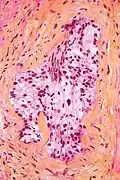

Micrograph showing a prostate cancer (conventional adenocarcinoma) with perineural invasion. H&E stain.

In pathology, perineural invasion, abbreviated PNI, is the invasion of cancer to the space surrounding a nerve. It is common in head and neck cancer, prostate cancer and colorectal cancer.